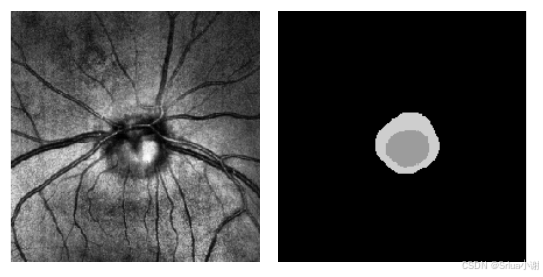

概述

在眼科学中,盘杯分割充当了评估视神经头结构和早期阶段诊断青光眼的基本步骤。该任务的目标是从扫描激光眼底成像(SLO)中预测一个分割图,区分背景视盘和杯体。此任务的成功依赖于分割模型的准确分割。

这里提出的Fairseg框架致力于消除分割模型对不同人口群体的“歧视”,以确保其在不同群体上盘杯分割任务的公平性。

该篇文章还开源了第一个用于医疗图像分割公平性研究的大型数据集,我已经下载好,并将网盘链接放置在了附件当中。